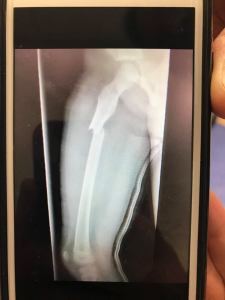

Nothing like a femur fracture to slow you down for awhile. Yup, zip it up better next time ๐ค

Even though for the time she was in much pain, and I hear femurs are the worse, it didn’t break her spirit.